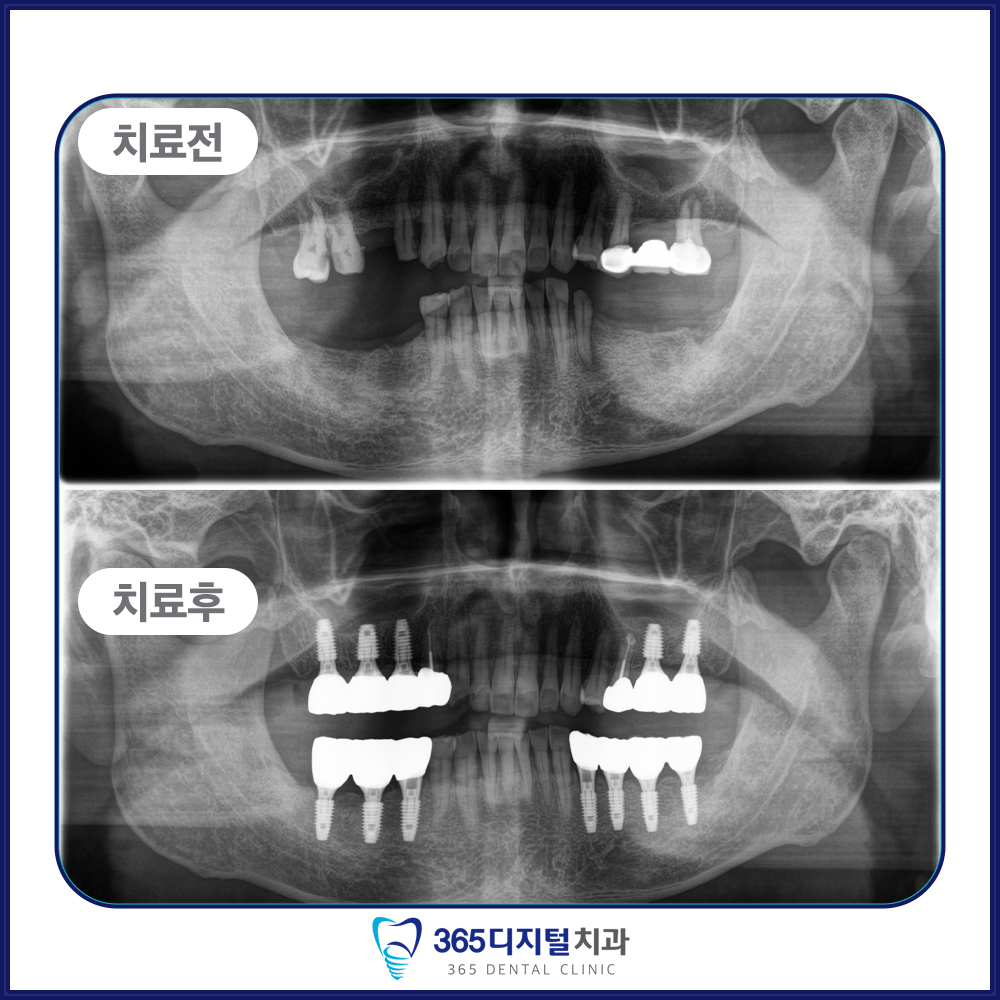

임플란트는 단순히 인공치아를 심는 것이 아닌,

환자의 삶의 질을 회복하는 진료라고 생각합니다.

오직 정밀한 진단과 정직한 진료만이

좋은 결과로 이어진다는 믿음으로

한 케이스, 한 환자에 깊이 집중합니다.

계획된 진단과 세밀한 설계,

그리고 환자 개인의 구강 구조에

맞춘 접근이 중요합니다.

– 임플란트 식립이 불가능하다고 들으신 분

– 뼈이식이 필요한 복잡한 케이스를 정밀하게 진행하고 싶은 분